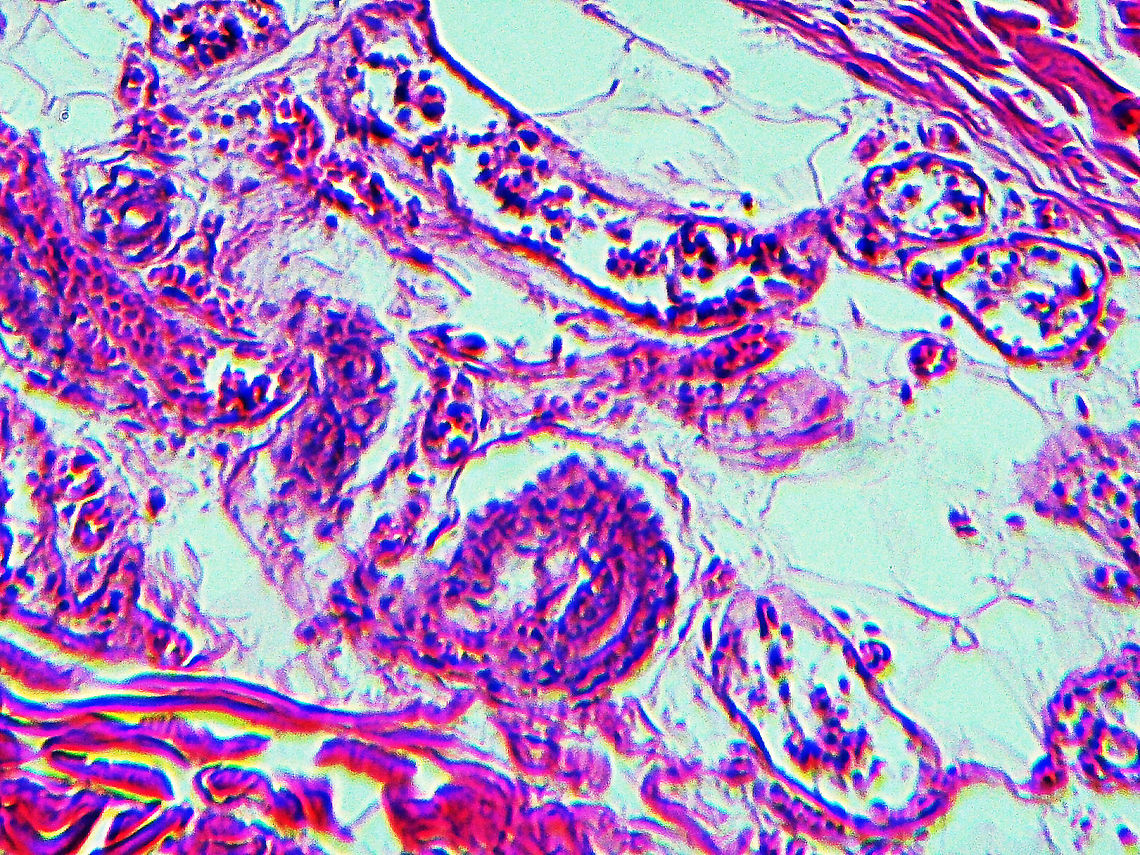

This slide is a skin biopsy from a person infected with Rickettsia rickettsii (the causative agent of Rocky Mountain Spotted Fever). It shows necrosis, vasculitis, and inflammation.